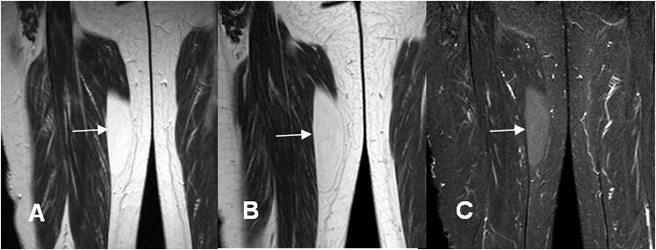

Fig 165. Fibrolipoma.

A: RM axial en T1, B: RM coronal en T1 y C: RM coronal en STIR. Lesión hiperintensa dentro del músculo biceps femoral. Su señal no es completamente hiperintensa, por algún componente fibroso y no suprime totalmente en el STIR.